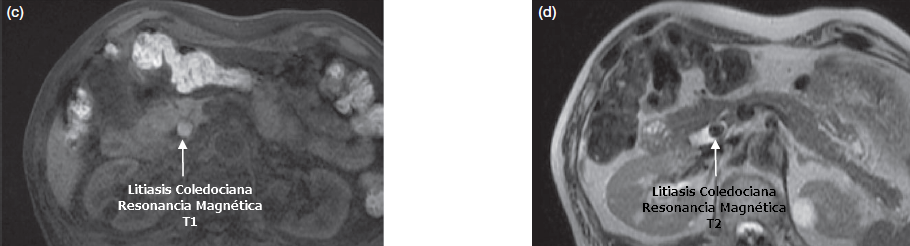

Resonancia Magnética

Se recomienda la Resonancia Magnética o Colangioresonancia para el diagnóstico de la etiología de la colangitis aguda